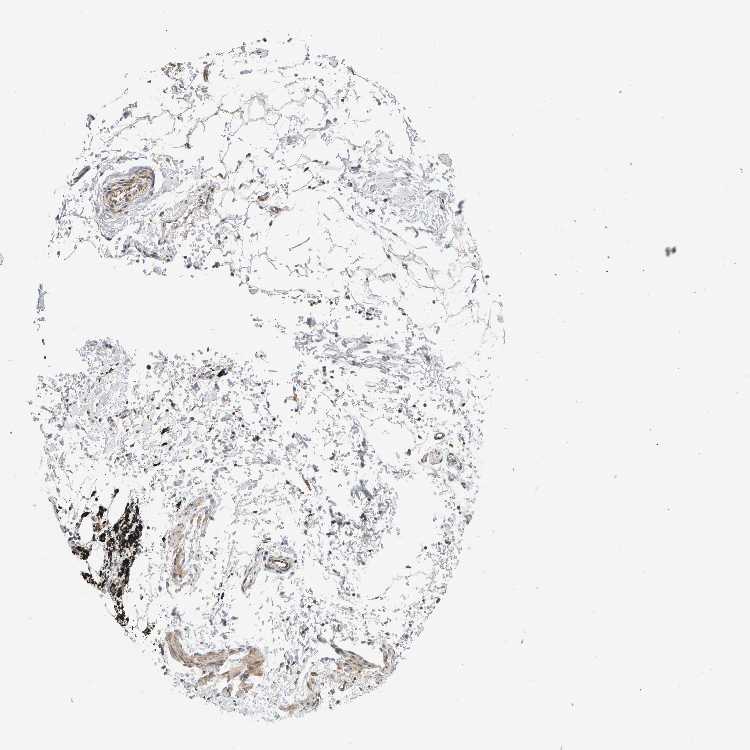

ADIPOSE TISSUE - Antibody stainingi

Antibody staining in the annotated cell types in the current human tissue is reported as not detected, low, medium, or high, based on conventional immunohistochemistry profiling in selected tissues. This score is based on the combination of the staining intensity and fraction of stained cells.

Each image is clickable and will lead to virtual microscopy that enables deeper exploration of all samples and also displays staining intensity scores, fraction scores and subcellular localization as well as patient and tissue information for each sample.

Antibody HPA023788

Adipocytes Not detected